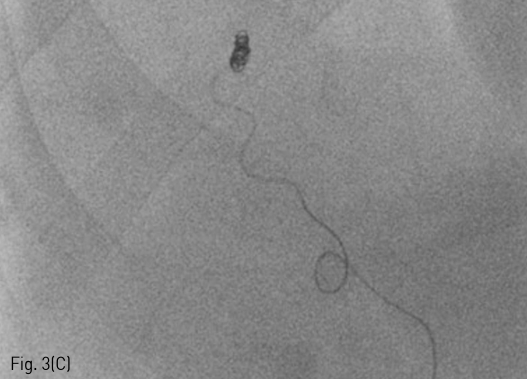

Fig 3C

(C) The shunt was embolized with detachable and pushable coils.